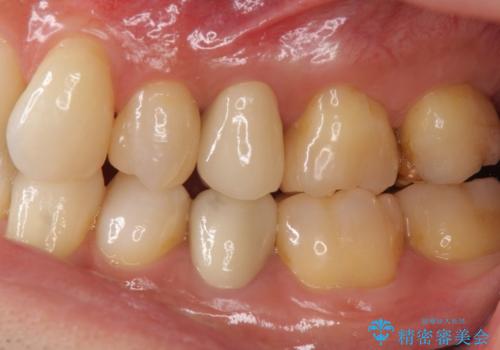

結果的には銀歯がすべて白くなり、前歯のガタつきもある程度改善され大変喜んでいただけました。

治療終了時からナイトガードを使用していただき、歯ぎしりによる破折を予防しています。